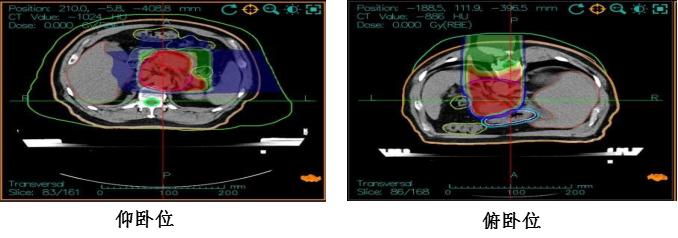

4、治疗方案:胰腺癌碳离子放疗,仰卧位三野轮照总剂量:41.4GyE,4.6GyE/fx;俯卧位PTVboost予以局部推量18.4GyE/4fx,4.6GyE/fx,总处方剂量:PTV 59.8GyE/13fx。治疗期间联合尼妥珠单抗注射液 400mg ivgtt d1周方案+吉西他滨 2.0g ivgtt d1、d8化疗。 治疗过程顺利,未出现明显不良反应,治疗后复查腹部MR提示:胰腺病灶缩小,疗效评价为PR。

5、碳离子治疗计划剂量云图及疗效评估: